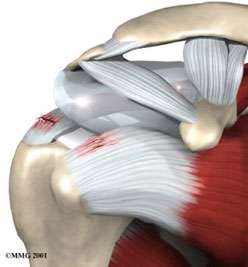

Βλάβη Bankart

Η βλάβη Bankart εχεί ως κύριο σύμπτωμα την πρόσθια κάτω ασταθεία.

Αυτή η αστάθεια έχει σαν αιτία το τραυματικό εξάρθρωμα ώμου ή

κάποιο χρόνιο μικροτραυματισμό. Το τραυματικό εξάρθρωμα, ιδιαίτερα

σε μικρές ηλικίες, οδηγεί συχνά σε καθ'έξιν εξάρθρημα (μέχρι 90%).

Γι' αυτό συζητείται, εάν κάθε πρώτο εξάρθρημα του ώμου πρέπει

να αρθρωσκοπείται, σε δραστήρια και νεαρά άτομα. Επίσης γνωρίζουμε

την άμεση σχέση της επιτυχίας μιας επέμβασης με τον αριθμό των

εξαρθρήματων που προηγήθηκαν.

Η βλάβη Bankart είναι η αποκόλληση του κάτω πρόσθιου τμήματος

του επιχείλιου χόνδρου. Στην επέμβαση γίνεται επανακαθήλωση αυτής

της βλάβης με την βοήθεια αγκυρών. Συγχρόνως γίνεται και μια μείωση

του όγκου του θυλάκου που έχει ξεχειλώσει από την αστάθεια.

Βλάβη Bankart πριν και μετά απο την αποκατάσταση